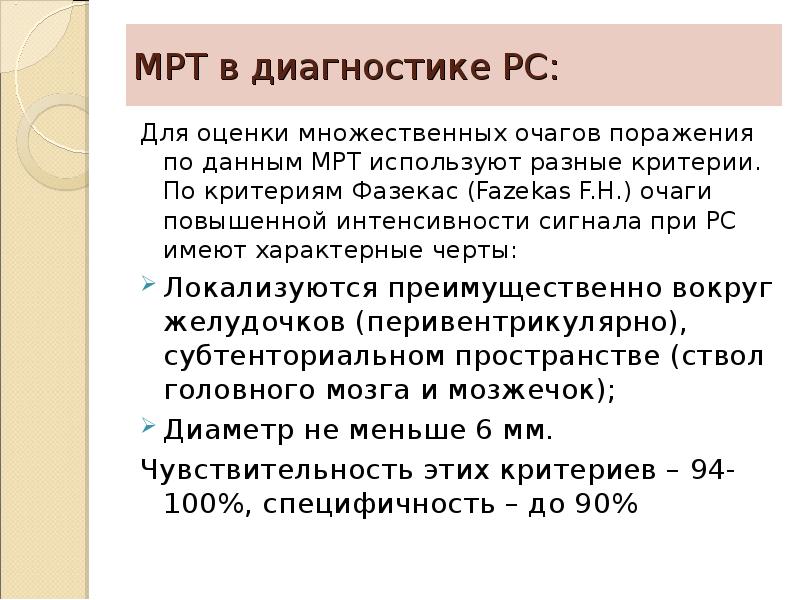

Fazekas grades. T1 t2 Flair. MRI t1 t2. T1 t2 мрт. T1 t2 fleur мрт.

Fazekas grades. T1 t2 Flair. MRI t1 t2. T1 t2 мрт. T1 t2 fleur мрт.

Fazekas grades. MRI t1 t2. Шкала Фазекас мрт. Очаги Фазекас мрт.

Fazekas grades. MRI t1 t2. Шкала Фазекас мрт. Очаги Фазекас мрт.

Fazekas grades. Фазекас мрт. Фазекас 2 мрт. Fazekas Scale MRI.

Fazekas grades. Фазекас мрт. Фазекас 2 мрт. Fazekas Scale MRI.

Fazekas grades. Dementia classification. Lesion traumtique cerebral classification.

Fazekas grades. Dementia classification. Lesion traumtique cerebral classification.